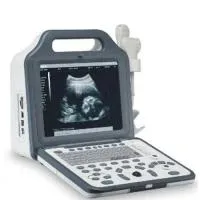

Ультразвуковой аппарат ветеринарный инструмент сканер для продажи на ферме

Ультразвуковой аппарат ветеринарный инструмент сканер для продажи на ферме

Ветеринарний УЗД сканер для свиней